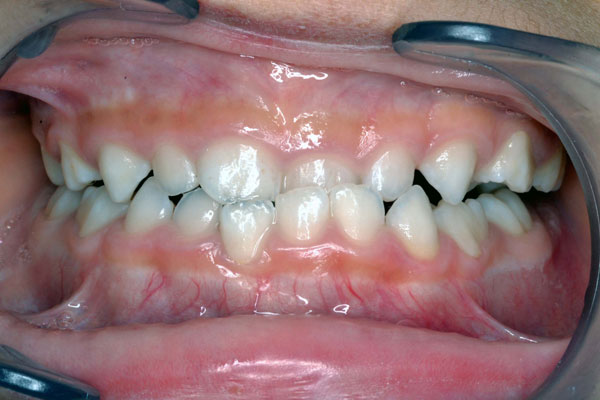

6才1ヶ月に治療開始

下の歯が前に出て生えて来てしまいました。